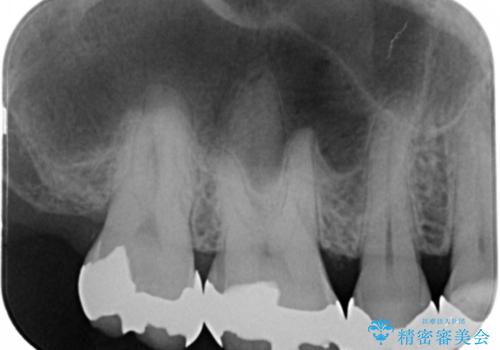

- かなり昔に入れた銀歯の部分のチェックをご希望でご来院されました。

上下ともに銀歯が多く入っており、その下に虫歯が疑われる状態でした。

詰め物の大きさや虫歯の状態から個々に材料と治療範囲を決定し治療に入りました。